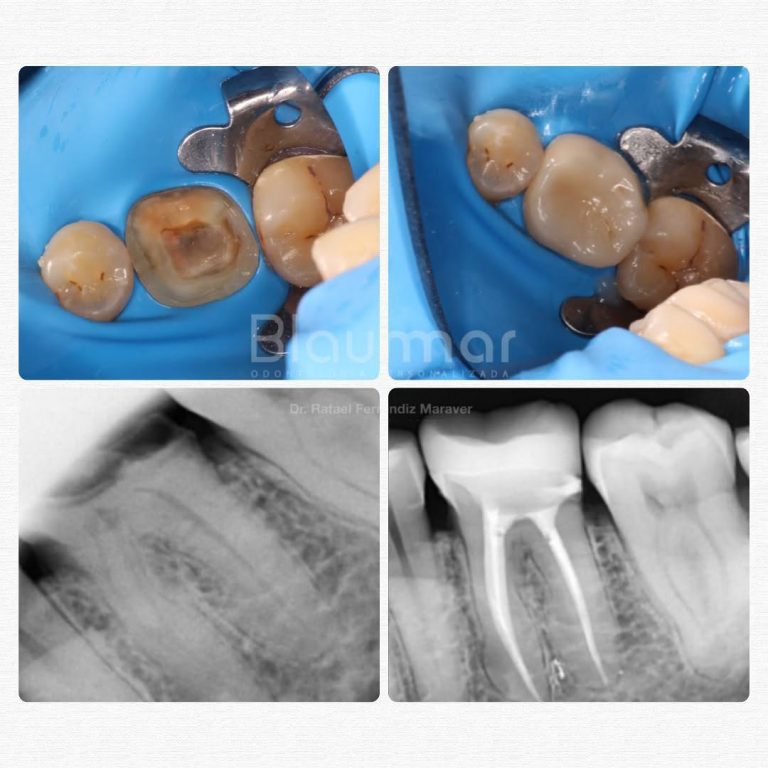

Casos reales de antes y después

Cada sonrisa tiene una historia. En Clínica Dental Blaumar te mostramos casos reales de pacientes que confiaron en nosotros para mejorar su salud y su estética dental. Antes y después, procesos y resultados explicados con claridad, para que veas cómo trabajamos: con planificación, precisión y un trato cercano de principio a fin.